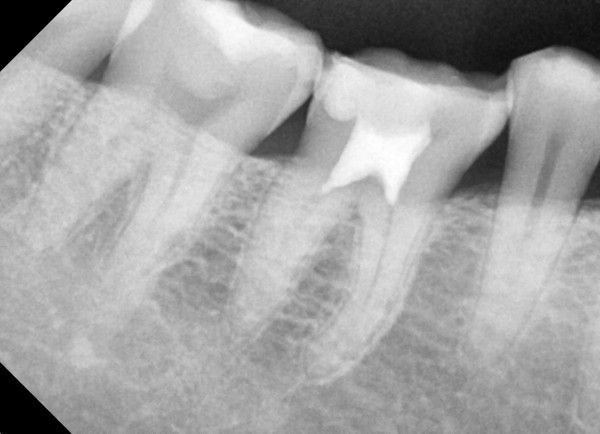

충치치료&신경치료 하루에 끝나는 신경치료

aa83206a7806dda7923c1af565c0c8ca_1767311913_3884.jpg